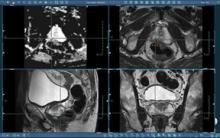

Prostate disease is primarily evaluated by using digital rectal examination (DRE) in combination with other clinical data including prostate-specific antigen (PSA) tests and pathologic information. These commonly used diagnostic tests have been shown to result in both high false positive and high false negative results.

November 4, 2010 – A new magnetic resonance (MR) imaging for oncology use was introduced at the American Society for Therapeutic Radiology and Oncology (ASTRO) meeting in San Diego, Calif. The Panorama High Field Open (HFO) Oncology Configuration, by Philips, combines the soft tissue contrast of MR with a spacious patient aperture.